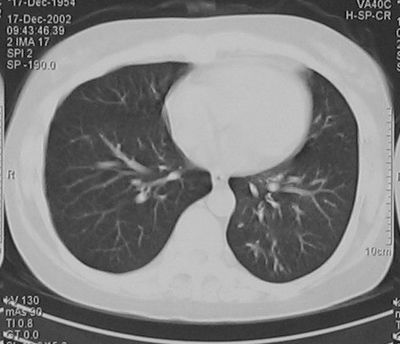

RP的胸部影像学检查 胸片显示可有呼吸道感染、肺不张及肺炎改变。CT由于具有较高的空间及密度分辨率,可以较好的显示气管及支气管病变范围、管壁厚度、管腔狭窄程度及纵膈淋巴结肿大,所以对于早期发现本病,改善患者的预后,有较高的价值。特别是CT三维重建可清楚显示管腔一系列临床病理改变。RP的主要CT表现为气管及主支气管管壁的增厚及管腔的狭窄。大气管受累包括胸廓外及胸廓内的部分,部分向上延伸可累及喉部软骨。在急性期,由于炎性水肿及肉芽组织增生,可导致气道壁的广泛增厚,其特征为以大气管的前、侧壁增厚为主,而其后壁的膜部大致正常。增厚的大气管的内、外轮廓比较光整。长期反复发生慢性炎症,软骨破坏,可逐渐出现程度不等的管壁钙化[7-8]。(见后附图)

图4:左肺下叶继发感染呈多发斑片结节影

图5:经抗感染治疗后左肺下叶病变消失